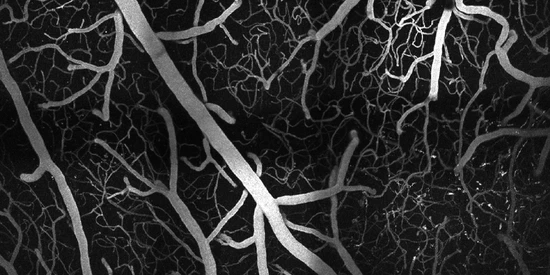

We design and build high-resolution microscopes to study the three-dimensional vascular and neuronal structures of the cortex at depths and resolutions pushing the limits of optical imaging.

We developed an automated vectorization method to extract blood vessel geometry and vascular statistics directly from large volumes of unsegmented multiphoton microscopy imagery.